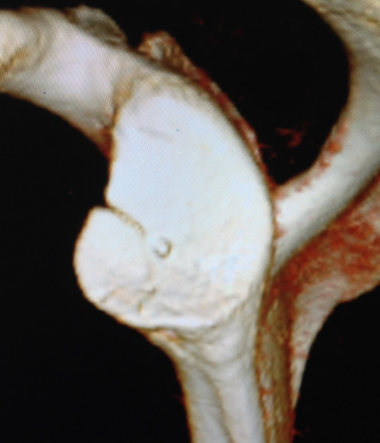

全镜下Bristow手术

在国际上首创关节镜下改良“嵌入式”喙突移位(Bristow)手术,并将其命名为CUIstow手术(Chinese Unique Inlay Bristow)